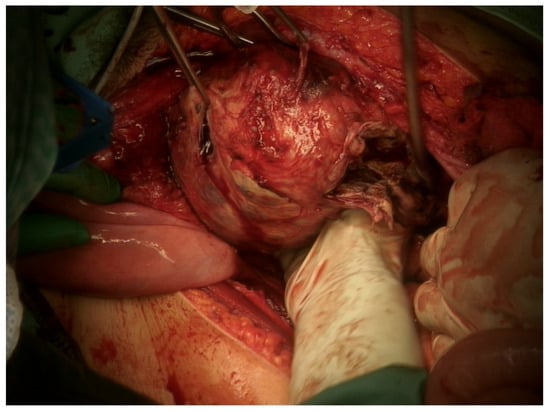

2. Case Presentation